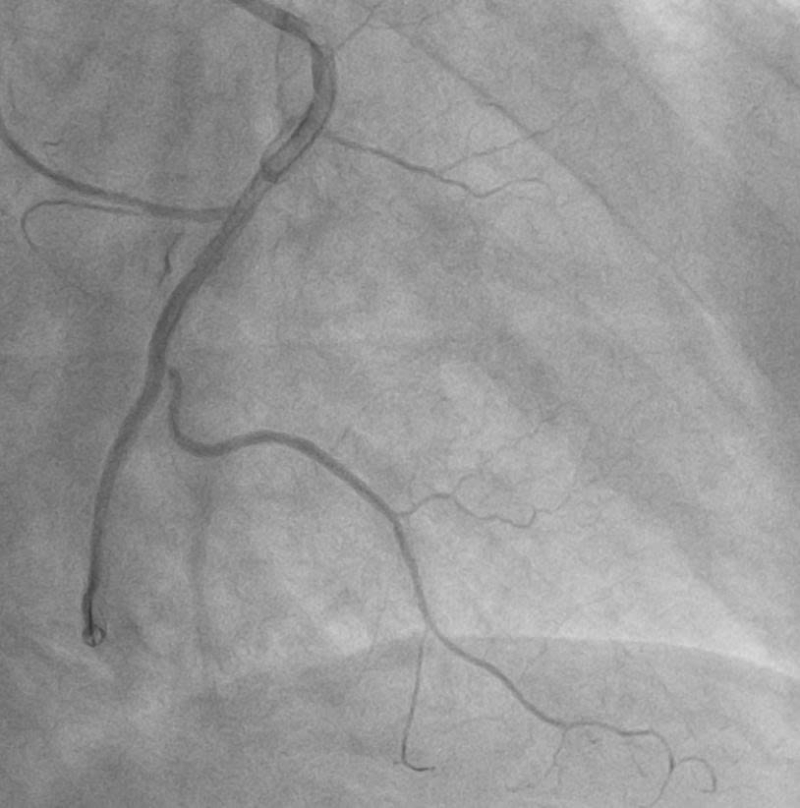

Ê-kíp can thiệp đã nhanh chóng triển khai nhiều biện pháp xử trí, trong đó có tiêm trực tiếp thuốc giãn mạch vào lòng động mạch vành như Adenosine nhằm giảm co thắt và cải thiện vi tuần hoàn. Sau khi xử trí tích cực, dòng chảy mạch vành đã được khôi phục với mức dòng chảy TIMI 2, giúp ổn định tình trạng cho người bệnh.

Hình ảnh: Sau can thiệp